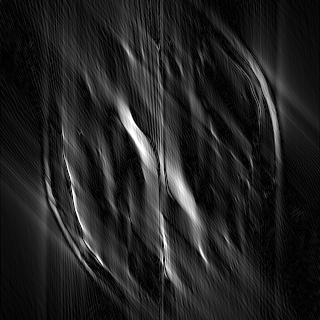

This article presents a novel undersampled magnetic resonance imaging (MRI) technique that leverages the concept of Neural Radiance Field (NeRF). With radial undersampling, the corresponding imaging problem can be reformulated into an image modeling task from sparse-view rendered data; therefore, a high dimensional MR image is obtainable from undersampled $k$-space data by taking advantage of implicit neural representation. A multi-layer perceptron, which is designed to output an image intensity from a spatial coordinate, learns the MR physics-driven rendering relation between given measurement data and desired image. Effective undersampling strategies for high-quality neural representation are investigated. The proposed method serves two benefits: (i) The learning is based fully on single undersampled $k$-space data, not a bunch of measured data and target image sets. It can be used potentially for diagnostic MR imaging, such as fetal MRI, where data acquisition is relatively rare or limited against diversity of clinical images while undersampled reconstruction is highly demanded. (ii) A reconstructed MR image is a scan-specific representation highly adaptive to the given $k$-space measurement. Numerous experiments validate the feasibility and capability of the proposed approach.